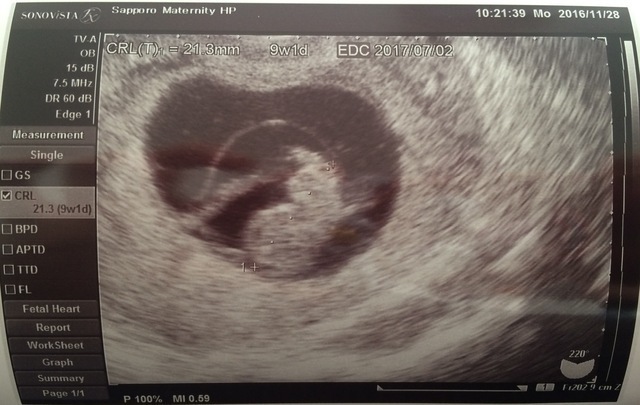

9週1日(9w1d・男の子)|プロ・カフェ さん(37歳)

エコー写真撮影時のエピソード:

初めての子どもでドキドキでした。人の形になってきたところで何となく人だなってわかりますよね。

つわりとかなかったので、焼肉屋とかにも行ってました。一般的につわりが治る頃に妊娠悪阻になって1週間寝たきりで救急で点滴してもらった思い出があります。